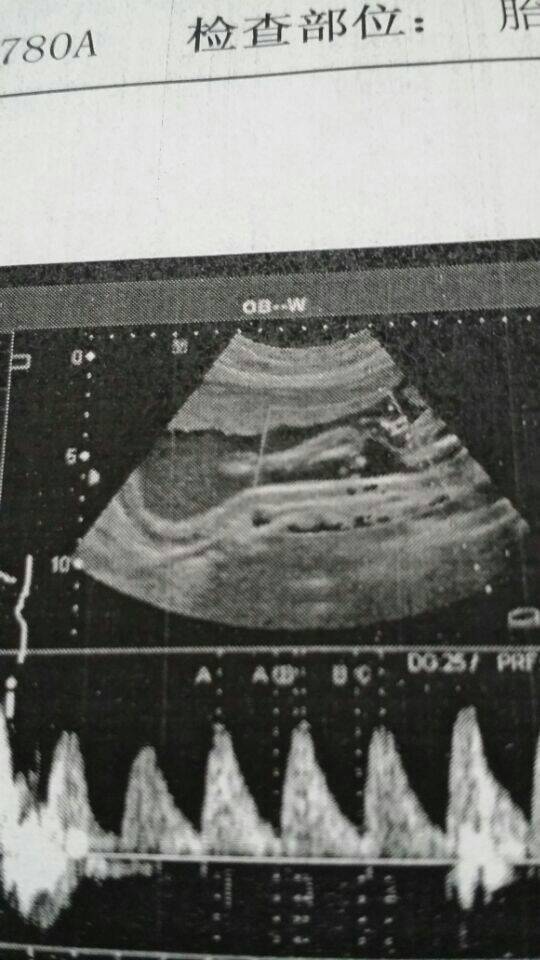

一般情况怀孕后18周后进行B超检查可以初步判断男女孩的,但不是100%准确的,准确率在80%左右,正规医院是不能检查,自私检查孩子性别是违法的,其他判断孩子性别是没有很好办法,根据怀孕后肚子,早孕反应,胎动,怀孕时间及其他情况是不能判断。